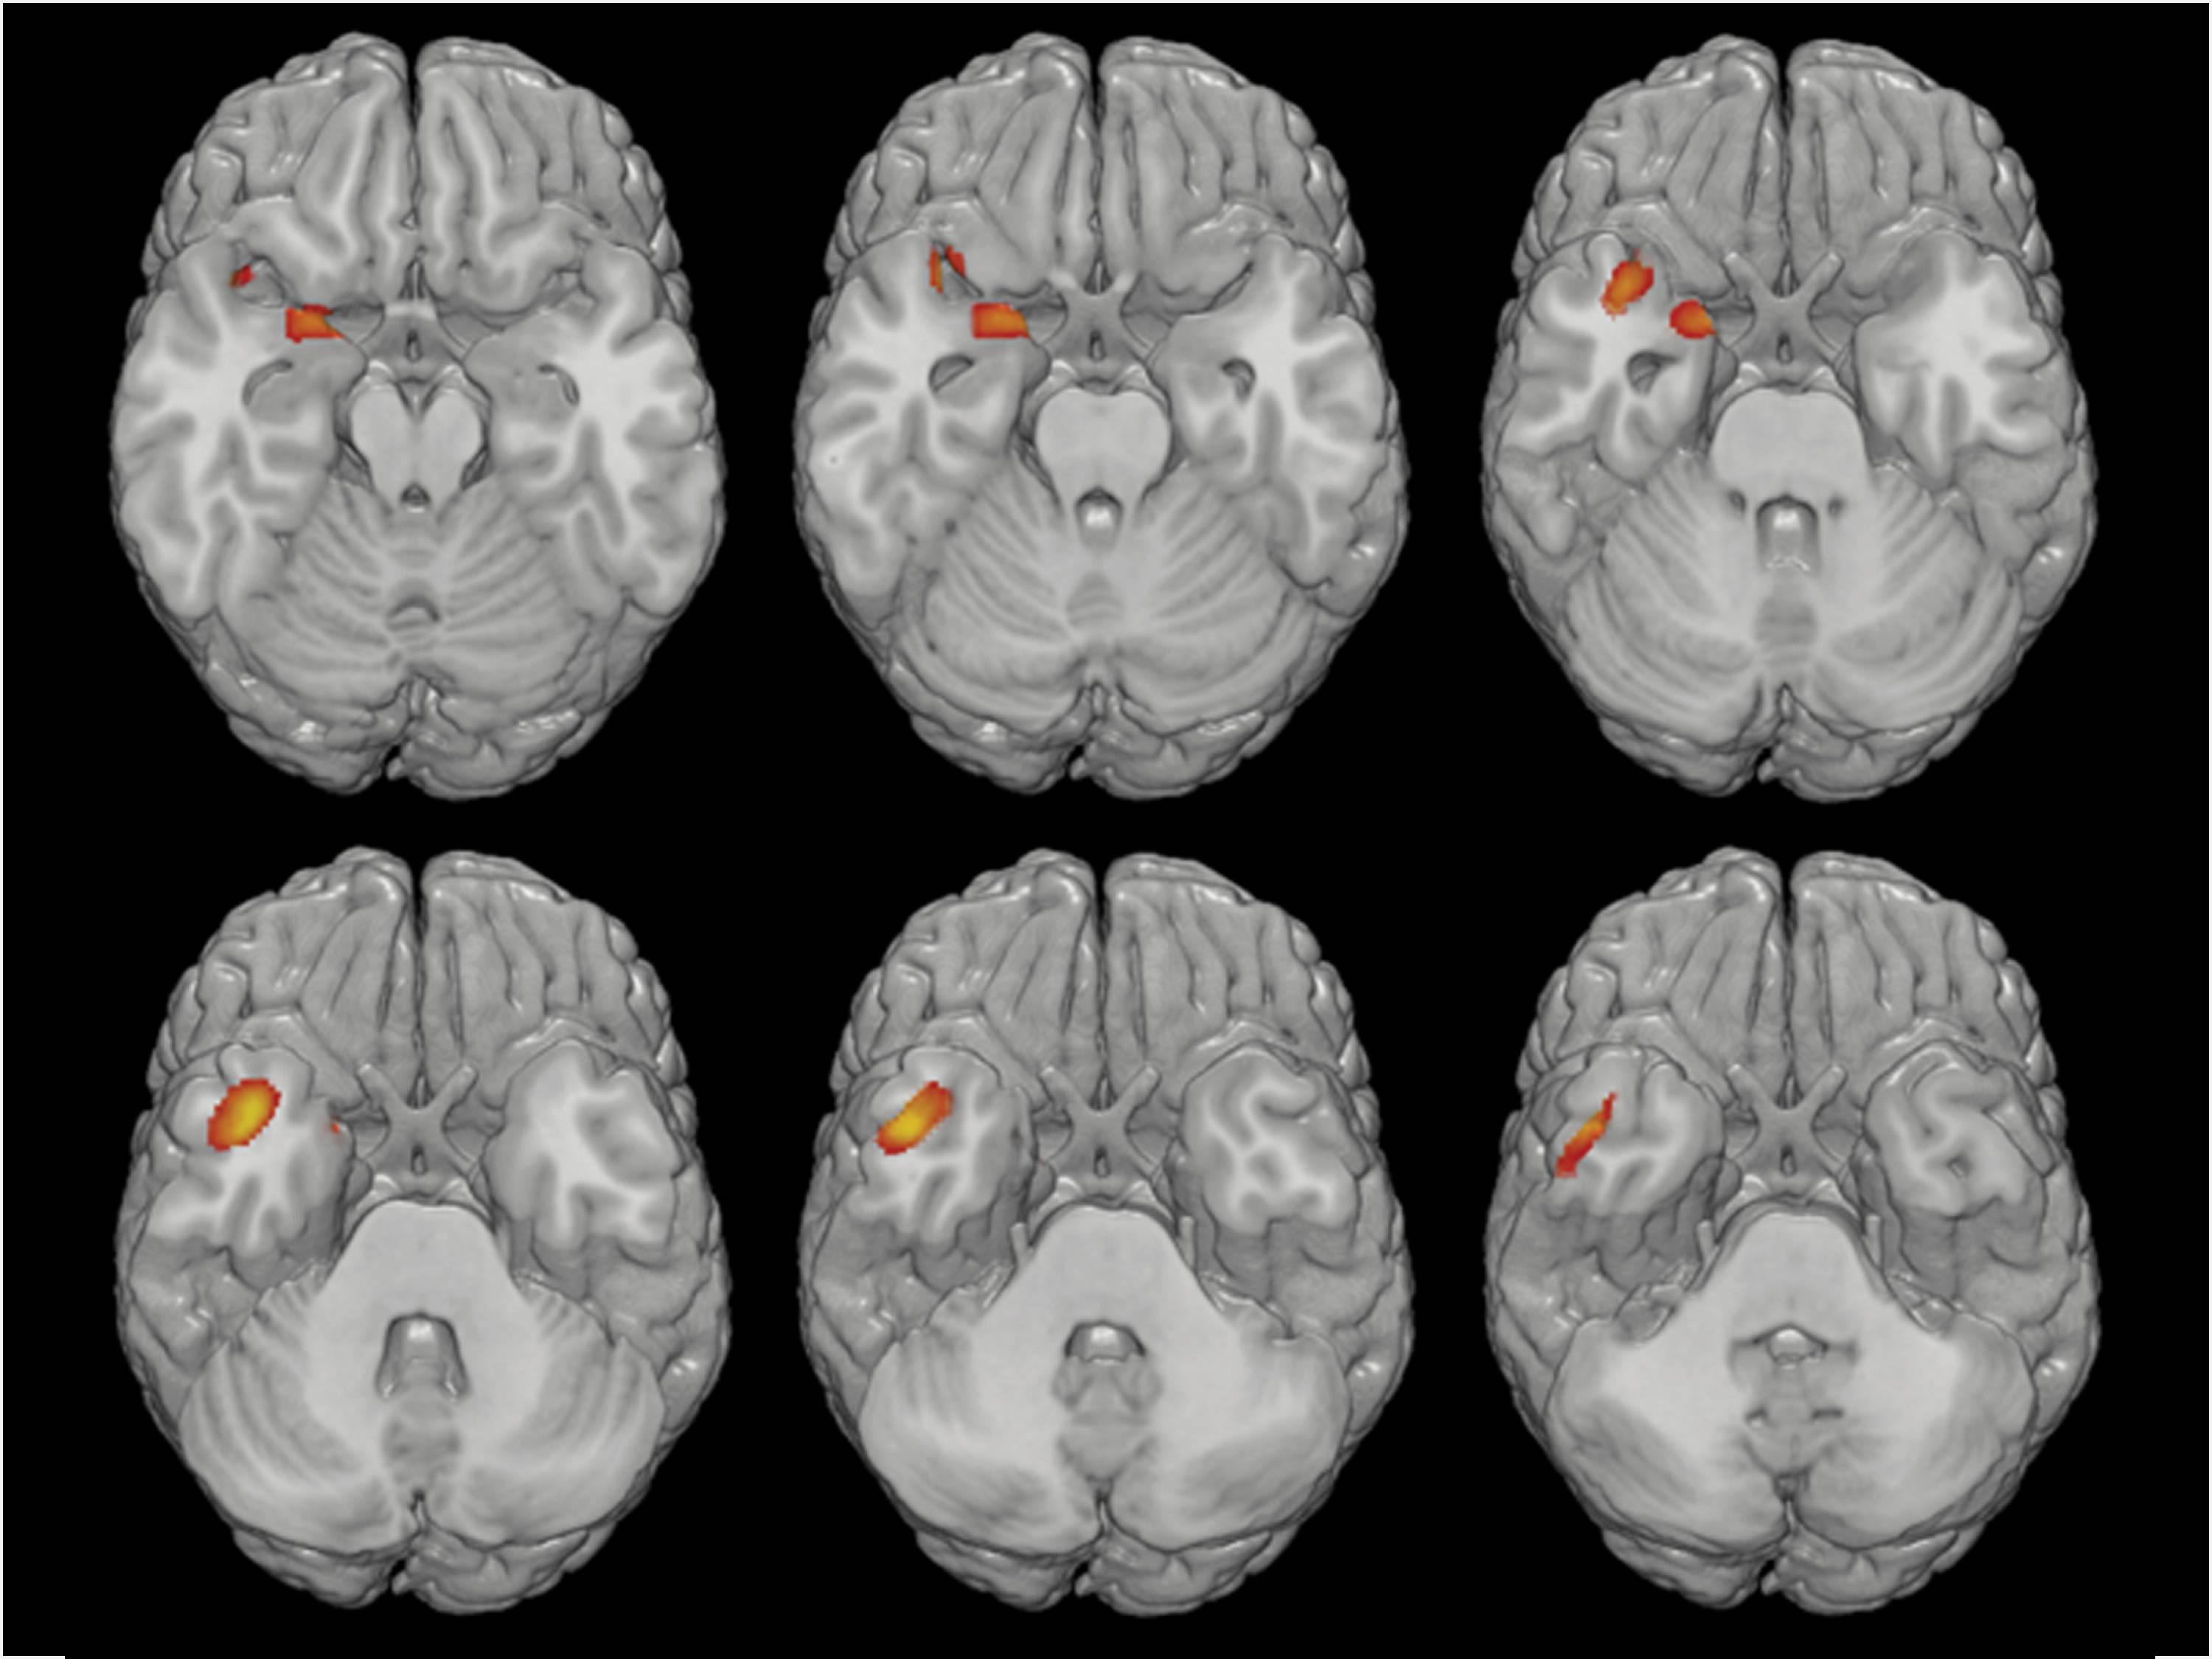

Según este estudio, el recuento de neutrófilos es más alto en los pacientes con PEP en comparación con los controles sanos y se evidencia una pérdida de materia gris asociada a esta cantidad, principalmente en las zonas del tálamo, ínsula, corteza entorrinal y giro temporal.

Los resultados del estudio ponen de manifiesto el papel de la desregulación inmune periférica en la enfermedad mental. A raíz de otras investigaciones, los autores proponen la presencia de neutrófilos en el tejido cerebral como biomarcador de la severidad de la psicosis, ya que parece ser uno de los principales desencadenantes de la perdida de volumen cerebral y del consiguiente declive clínico y cognitivo en estas enfermedades. También se abre la puerta a posibles tratamientos basados en bloquear la entrada de neutrófilos en el cerebro, aunque será necesario investigar más a fondo en esta línea para evaluar la viabilidad de este tipo de intervenciones.